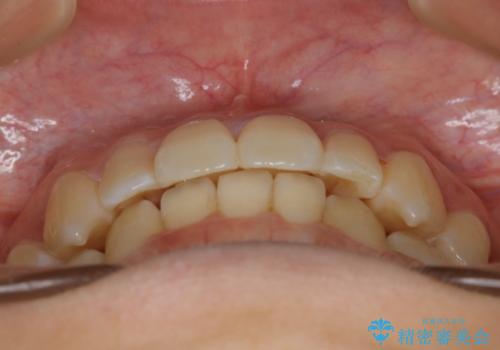

下顎前歯の先天欠損と上顎前歯のクロスバイト:インビザライン治療

- 上の前歯が1本後ろに入ってしまっていることが気になるとご相談にいらした方です。

クロスバイトしている歯が深く噛み込んでおり、この歯を外に出してくる際に強い咬合力が加わると歯が失活する恐れがあることを説明し、合わせて咬筋へのボトックス注入を行いました。

下顎切歯が1本欠損しているため、上顎前歯部を少しずつストリッピングして、上下の噛み合わせ、バランスの向上を図りました。